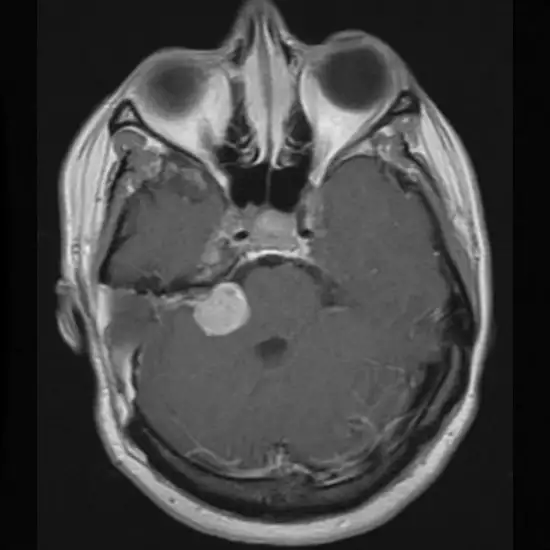

MRI CP Angle

MRI Brain CP Angle is utilized to evaluate the cerebellopontine angle, a spinal fluid-filled region. Its medial limit is the brain stem, its roof, and a posterior barrier is a cerebellum, and its lateral boundary is the posterior surface of the temporal bone.

The physician suggests this test to diagnose traumatic brain injury (TBI), detect the presence of stroke, and detect the presence of a brain tumor.